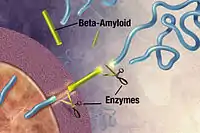

Alzheimer's disease has been identified as a protein misfolding disease, a proteopathy, caused by the accumulation of abnormally folded amyloid beta protein into amyloid plaques, and tau protein into neurofibrillary tangles in the brain.[93] Plaques are made up of small peptides, 39–43 amino acids in length, called amyloid beta (Aβ). Amyloid beta is a fragment from the larger amyloid-beta precursor protein (APP) a transmembrane protein that penetrates the neuron's membrane. APP is critical to neuron growth, survival, and post-injury repair.[94][95] In Alzheimer's disease, gamma secretase and beta secretase act together in a proteolytic process which causes APP to be divided into smaller fragments.[96] One of these fragments gives rise to fibrils of amyloid beta, which then form clumps that deposit outside neurons in dense formations known as amyloid plaques.[88][97]